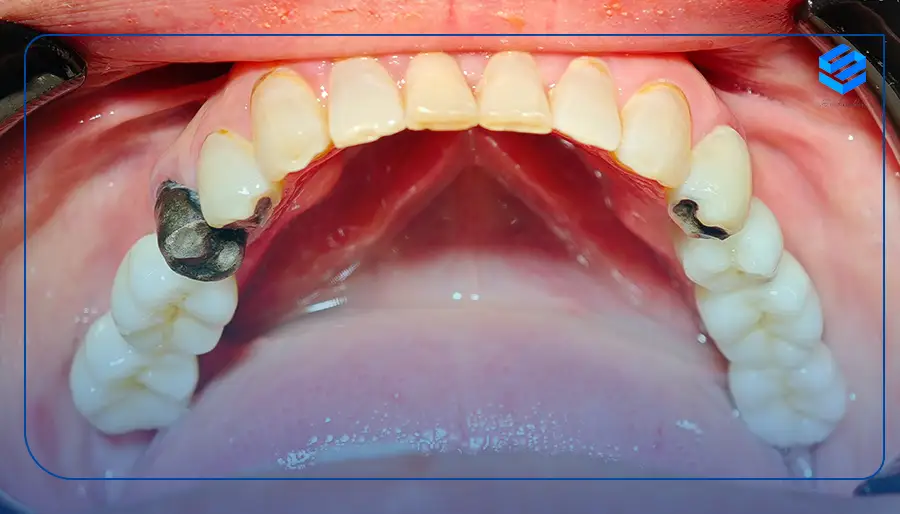

ایمپلنت دندان ( dental implant ) یک درمان برای پر کردن جای خالی دندان های از دست رفته با بیش از 97% موفقیت است که یک پایه فلزی به شکل پیچ جایگزین ریشه دندان از دست رفته شده و به استخوان فک جوش می خورد و شامل سه جزء فیکسچر، اباتمنت و روکش می باشد.

از ایمپلنت دندانی برای جایگزینی یک دندان تا تمام دهان استفاده می شود و این روش از تحلیل استخوان و لثه جلوگیری می کند. همچنین این درمان دارای بالاترین طول عمر ، استحکام و بیشترین شباهت به دندان طبیعی می باشد. برای بررسی دقیق تر ایمپلنت دندان با ما همراه باشید.

ایمپلنت دندان (Dental Implant) روشی موثر و کارآمد برای جایگزینی دندانهای ازدسترفته است. ایمپلنت پایهای محکم برای دندانهای ثابت و یا متحرک فراهم میکند. در این تکنولوژی پیشرفته پایهای معمولا از جنس فلز تیتانیوم یا مواد بیولوژیکی سازگار با بدن انسان، بهعنوان ریشه مصنوعی دندان در استخوان فک جایگذاری میشود.

از نظر دکتر سعیدیان،بهترین دکتر ایمپلنت در نیاوران ایمپلنت یک جسم خارجی محسوب نمیشود و با قرارگرفتن در استخوان فک بیمار به مرور زمان به فک جوش خورده و با آن سازگار میشود. اگر پس از قرارگرفتن ایمپلنت در فک به طور صحیح از آن نگهداری و مراقبت شود، ماندگاری و طول عمر بالایی خواهد داشت.